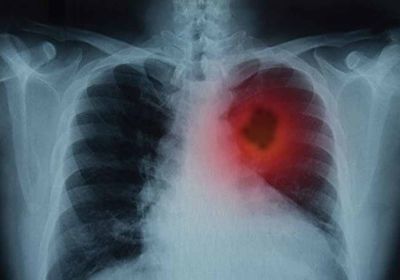

सांसों पर हमला: स्मोकिंग के साथ एयर पॉल्यूशन भी बड़ा जोखिम, इन लक्षणों को न करें इग्नोर

24 Nov, 2025 10:21 AM IST | SAMWADINDIA.INनवंबर लंग कैंसर अवेयरनेस महीने के रूप में मनाया जाता है। यह मौका है लोगों...

फेफड़ों के कैंसर से लड़ाई में नई उम्मीद! शोध में ट्यूमर 80% तक कम करने की सफलता

22 Nov, 2025 02:36 PM IST | SAMWADINDIA.INफेफड़ों के कैंसर से जूझ रहे लाखों लोगों के लिए विज्ञान की दुनिया से एक...